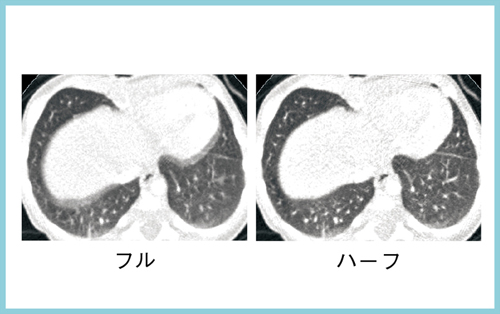

1回での広範囲の撮影は,小児の胸部撮影でもメリットが大きい。小児の撮影では,通常のヘリカルスキャンでは高速撮影を行っても呼吸や心臓の動きによって位相が変わり,バンディングアーチファクトが発生する。Aquilion ONEでは,1回のボリュームスキャンとハーフ再構成によって時間分解能が向上し,ブレの少ない画像が得られる(図3)。

図3 小児撮影でのボリュームスキャンとハーフ再構成による胸部画像